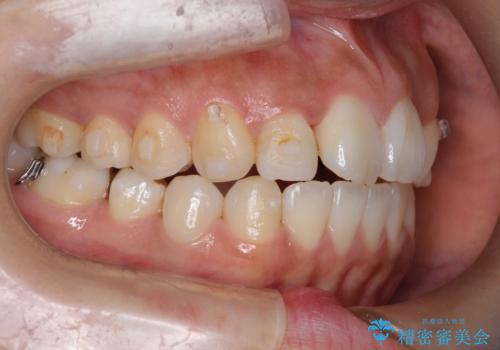

【引っ込んだ前歯が気になる、真ん中の線も揃えたい】インビザライン症例

- 前歯の歯並びの改善を希望され来院された患者様です。

初診時の歯並びの状態としては、上下ともに全体に及ぶの中等度のがたつき(叢生)があり、全特に左上の前歯は1本だけ引っ込んでいる状態でした。

抜歯は行わず上顎の奥のスペースを利用して歯をスライドする方法の他に歯列弓の拡大やディスキング(歯と歯の間の隙間を作る処置)を行い叢生を改善しました。

歯の大きさの不揃いが原因の正中のズレは、ディスキング量を調整することで合わせました。